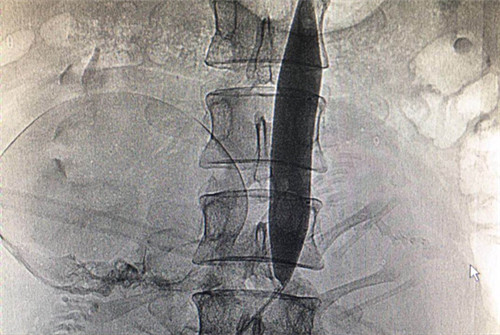

介入科李建国主任与何彤副主任急诊行右股动脉穿刺成功后行腹主动脉造影,经测量分析置入20mm×4cm大球囊,远端定位于髂总动脉分叉上方(L4),在腹主动脉球囊扩张临时阻断下行剖宫产手术。剖宫产手术顺利,胎儿及胎盘娩出后经严密观察子宫切口及阴道无异常出血倾向,顺利关腹并撤出球囊,术中出血量约400ml,产妇及胎儿生命体征平稳,成功保留了患者子宫。手术过程有惊无险,严密有序,通过大家的共同努力手术取得了圆满成功。